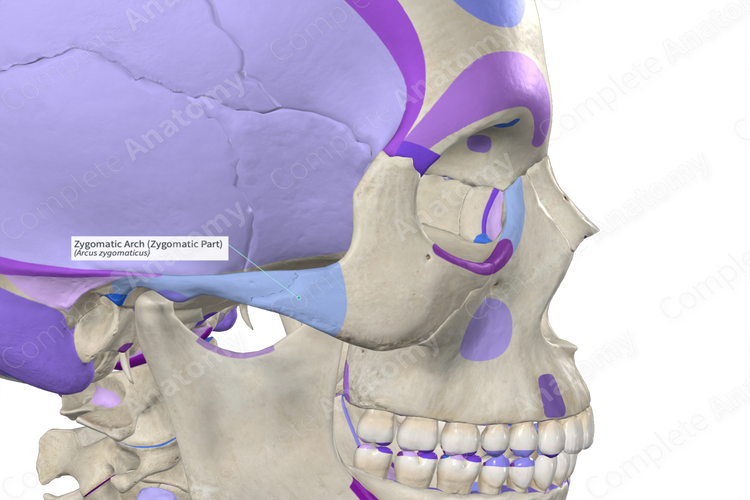

step 7 : perform the tripod osteotomy and expand the width of the orbitals, but something is confusing me about the tripod, how you gonna make lateral orbital rims more setback without causing conflict/problems with the zygomatic arch?

step 7 : perform the tripod osteotomy and expand the width of the orbitals, but something is confusing me about the tripod, how you gonna make lateral orbital rims more setback without causing conflict/problems with the zygomatic arch?